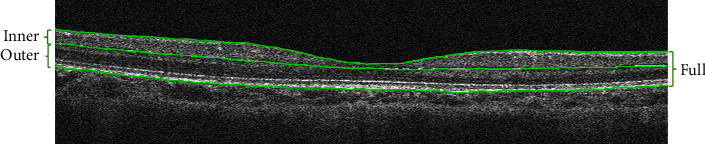

Methods: The study included 1161 eyes of 708 myopic children, with 616 (53.06%) right eyes and 545 (46.94%) left eyes. The participants underwent a comprehensive ophthalmic examination, including visual acuity, axial length (AL), autorefraction, and optical coherence tomography (OCT) examination in 2016 and in 2017. An analysis was conducted on the differences in retinal thickness between different genders and between high myopia and nonhigh myopia. Furthermore, the study delved into the correlation between the progression of myopia and the changes of retinal thickness.

Results: The average diopter was -1.83 ± 1.29D, average AL was 23.78 ± 0.94 mm, and average foveal thickness was 228.02 ± 23.00 μm. For the inner retina, the median value [the lower quartile value, the upper quartile value] of the foveal thickness was thicker in the high myopia group than the nonhigh myopia group (67 [64; 74] μm vs. 63 [56; 70] μm), while the parafoveal region and perifoveal region were thinner in the high myopia group than the nonhigh myopia group (106 [100; 123] μm vs. 124 [117; 130] μm; 95.0 [93; 102] μm vs. 104 [100; 108] μm). Among all the children with myopia, 67.53% (784/1161) of them have a diopter progression within one year. The AL progression was 95.43% (1108/1161). The retinal thickness of all children has slightly increased in various regions. As the AL of the eye increased and the diopter decreased, the progression degree of inner retinal thickness and full retinal thickness (exclusive of full fovea) decreased.

Conclusion: For the school-age myopic children, the inner foveal retinal thickness were thicker in highly myopic students than in the nonhighly myopic students, while the parafoveal and perifoveal retina were thinner in highly myopic students. The inner and full retinal thicknesses of male students were thicker than that of females. The progression of myopia mainly affected the changes of the inner retinal thickness in the one-year follow-up.